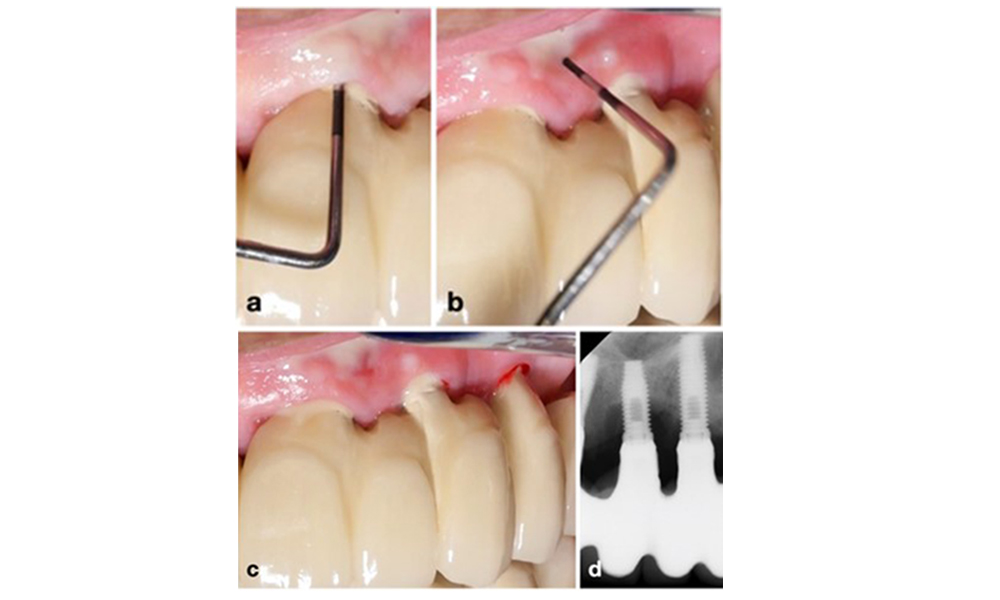

The World Workshop on the Classification of Periodontal and Peri‐Implant Diseases and Conditions from 2017 established diagnostic criteria for peri-implant mucositis and peri-implantitis (Renvert et al. 2018). Peri-implant mucositis is defined as (1) presence of inflammation around the implant (i.e., redness, swelling, line or drop of bleeding within 30 seconds of probing), combined with (2) no additional bone loss after initial healing (figure 1).

Implant in position 26 with peri-implant mucositis (a–c). The probing depth value of 5 mm (b) remains consistent with the measurement taken a few weeks after placing the prosthetic reconstruction. There is bleeding on probing (c) but the radiograph indicates no additional bone loss beyond what is expected for marginal bone remodelling (d).

Figure 1. Implant in position 26 with peri-implant mucositis (a–c). The probing depth value of 5 mm (b) remains consistent with the measurement taken a few weeks after placing the prosthetic reconstruction. There is bleeding on probing (c) but the radiograph indicates no additional bone loss beyond what is expected for marginal bone remodelling (d).